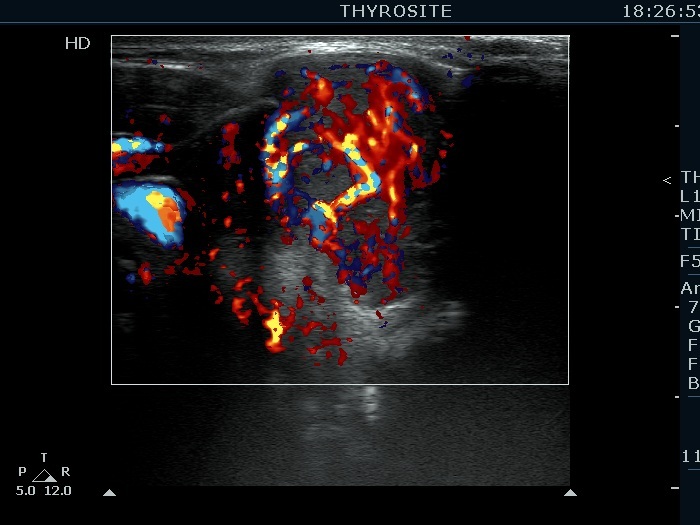

Extrathyroidal spread - case 2113 (ultrasonographic picture 7)

Right lobe, another transverse scan, color Doppler mode. A chaotic-type vascular pattern is demonstrated.